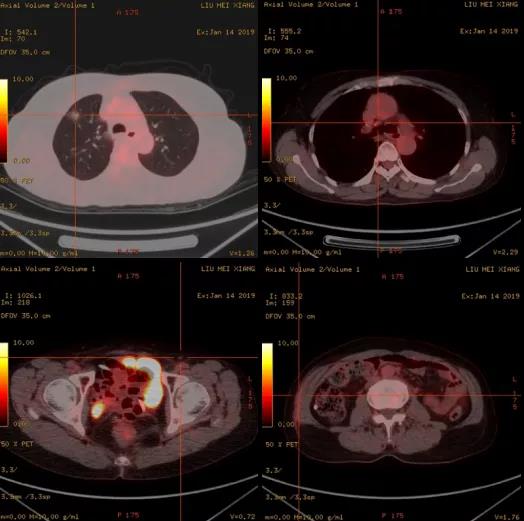

口服阿帕替尼第二个月,患者CA-125升高至87.5 U/ml(图4)。行PET-CT提示:1.右肺上叶磨玻璃影,部分代谢轻度增高,较前相仿,考虑为肿瘤性病变可能。2.阴道残端代谢无增高。3.腹膜后、双侧腋窝及双侧腹股沟区炎性或非特异性小淋巴结可能。4.右侧腰侧腹、右侧盆壁皮下片絮状影,代谢轻度升高,考虑炎性改变可能(图5)。结合病史,仍考虑为生化复发。为进一步延长PFI,给予患者口服替吉奥 50 mg,一天两次,连续14天,间隔7天。继续监测CA-125变化情况。

图5 患者生化复发后PET-CT结果